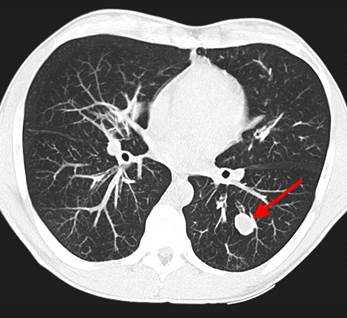

Метастазы в легких на КТ

Гематогенные метастатические узлы в легких на КТ имеют довольно четко очерченные и ровные контуры. Нечеткие, расплывчатые или лучистые контуры наблюдаются в том случае, если есть инвазивный рост в окружающую легочную ткань. Локализуются преимущественно в нижних, периферических отделах легких, хаотично, без очевидной связи с бронхами и крупными легочными сосудами.

Вторичные узлы гематогенного характера чаще всего имеют ровные края, четкие контуры и однородную структуру. Возможны изменения структуры опухоли вследствие кровоизлияния в паренхиму, обызвествлений, некроза центральной части узла, а также рубцов. Края узла могут стать нечеткими, расплывчатыми, если опухоль провоцирует отек легочной паренхимы, либо «лучистыми», если имеет место опухолевый лимфангиит.

Чаще всего метастазы выглядят как множественные очаги. Одиночные вторичные узлы крайне редки и встречаются меньше чем в 5% случаев. Чем больше узлов выявлено, тем выше вероятность их метастатической природы. Одиночный метастаз нужно дифференцировать с первичным раком, для этого обычно требуется тканевое исследование после оперативного вмешательства или биопсии.

Гематогенные метастазы наиболее часто локализуются в периферических отделах легких, вдали от крупных сосудисто-бронхиальных пучков, вблизи плевральной оболочки. При множественных поражениях гематогенного характера наблюдается тенденция к увеличению количества очагов в направлении «сверху-вниз». Чаще гематогенные метастазы расположены хаотично, вне четкой связи с бронхами и видимыми легочными сосудами. Практически не бывает такого, чтобы гематогенные вторичные узлы находились только с одной стороны, или занимали только одну долю или сегмент. При наличии такого распределения в первую очередь нужно думать о туберкулезе (верхние доли), множественных абсцессах и т. д.